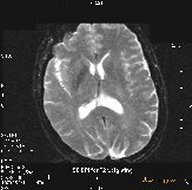

Spin Echo EPI

EPI uses multiple oscillating gradient “pulses” within a TR period, rather than RF to create the echo. A SE EPI protocol produces contrast similar to a standard SE image with the same TR and TE.

SE EPI is typically used to acquire T2-weighted scans. It can also be combined with the IR Prepared Imaging Option to acquire T1-weighted or IR images.